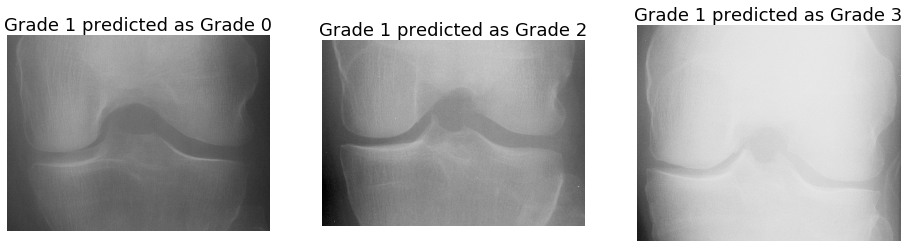

5.3.3 Error Analysis:

From the classification metrics (Table 5), the confusion matrix (Figure 9) and the receiver operating characteristics (Figure 9), it is evident that classification of successive grades is challenging, and in particular classification metrics for grade 1 have low values in comparison to the other Grades.

Figure 10 shows some examples of mis-classifications: grade 1 knee joints predicted as grade 0, 2, and 3. Figure 11 shows the mis-classifications of knee joints categorized as grade 0, 2 and 3 predicted as grade 1. These images show minimal variations in terms of joint space width and osteophytes formation, making them challenging to distinguish. Even for the more serious mis-classifications in Figure 12, e.g. grade 0 predicted as grade 3 and vice versa, do not show very distinguishable variations.

Refer to caption

Figure 10: Mis-classifications: grade 1 joints predicted as grade 0, 2, and 3